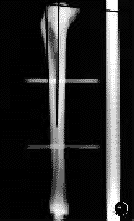

(一)X线投照:将胫骨依次固定于支架上,统一定位,放置一标准X线刻度尺,球管距离100cm,摄侧位片备用(图1)。

图1X线片髓内、髓外测量图

(一)X线片髓内测量:模拟手术的髓内定位法,测量胫骨平台前后缘连线与髁间棘前缘和髓腔最狭窄处中1/2连线的角度(图1)。

(二)X线片髓外测量:测量胫骨平台前后缘连线与胫骨结节上方和胫骨前缘骨皮质连线的角度(图1)。